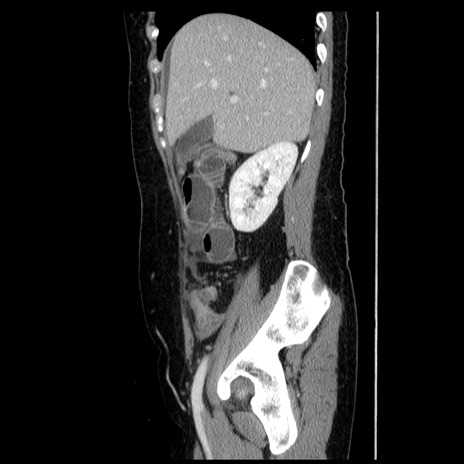

症例6(矢状断像)

【症例】50歳代女性

【主訴】下腹部痛

【現病歴】本日朝より下痢2回あり。 昼食を食べた後、嘔吐3回、下腹部痛認め、症状軽快せず、当院救急搬送。

最終食事:本日昼(生ものなし)。 昨日の夜、刺身を食ぺたとのこと。周囲に同様の症状の者なし。普段、排便は毎日あるとのこと。

【既往歴】卵巣癌術後(8年前に当院で卵巣摘出)

【身体所見】 意識清明、腹部:平坦、腸蠕動音→、やや硬、下腹部自発痛・圧痛あり、反跳痛あり、筋性防御なし。

【データ】WBC 16000、CRP 0.01